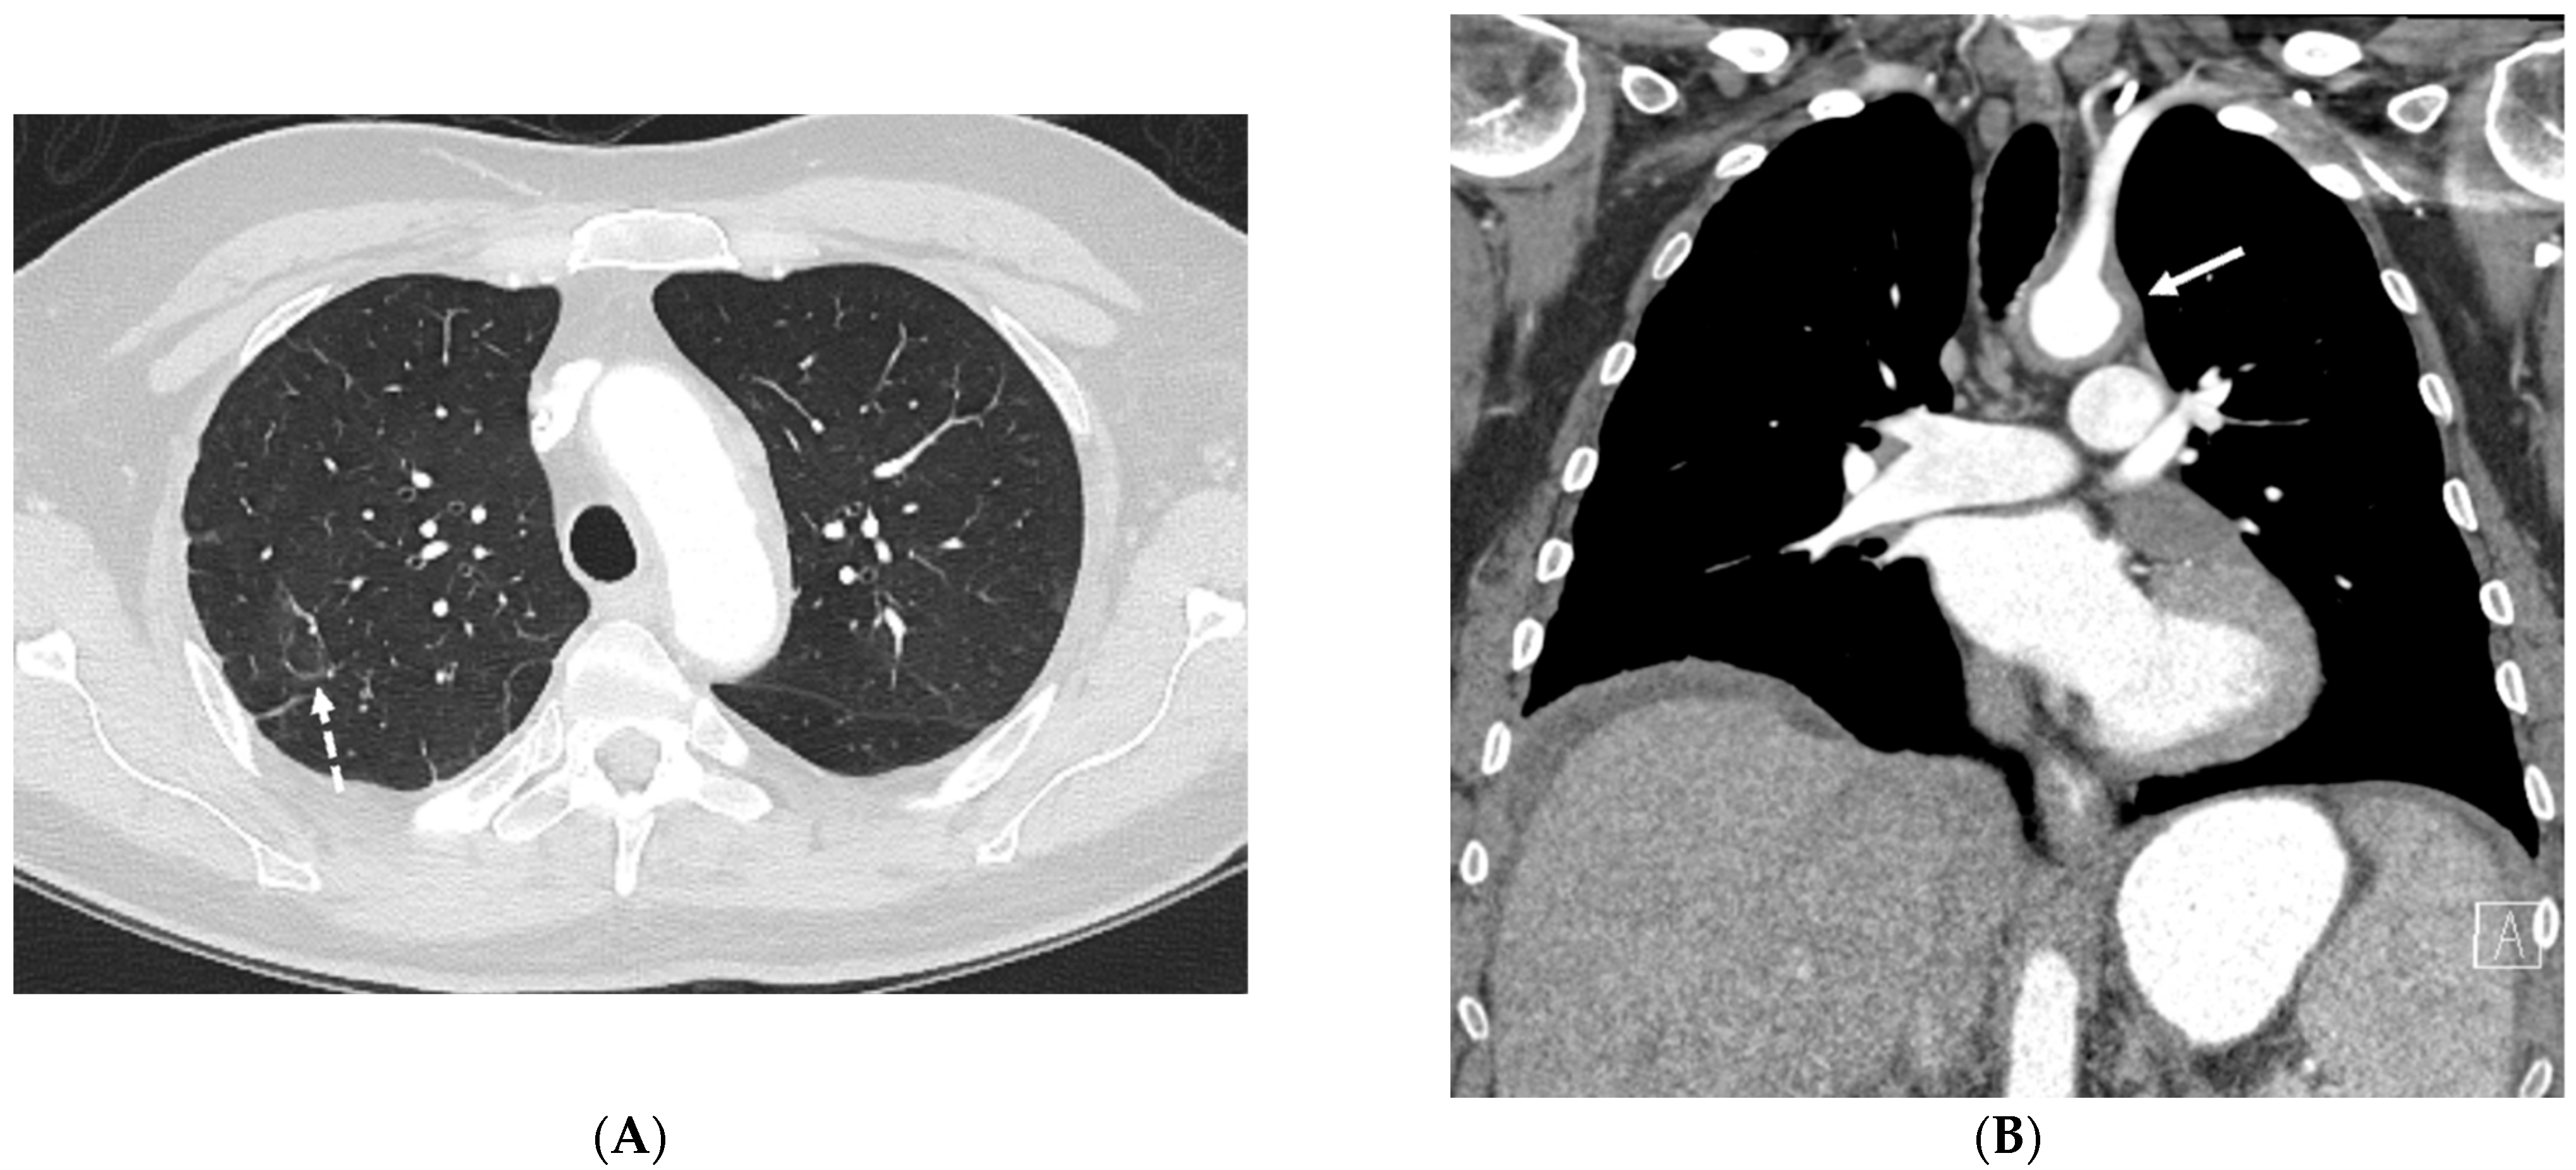

4.7. Pulmonary Vein Stenosis (PVS)

7.2. Pulmonary Capillary Hemangiomatosis (PCH) and Pulmonary Veno-Occlusive Disease (PVOD)

7.3. Diffuse Pulmonary Lymphangiomatosis

8.2. Granulomatous–Lymphocytic Interstitial Lung Disease (GLILD)

8.3. Granulomatosis with Polyangiitis (GPA)

8.4. Erdheim Chester Disease (ECD)